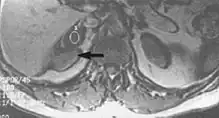

Metal artifacts occur at interfaces of tissues with different magnetic susceptibilities, which cause local magnetic fields to distort the external magnetic field. This distortion changes the precession frequency in the tissue leading to spatial mismapping of information. The degree of distortion depends on the type of metal (stainless steel having a greater distorting effect than titanium alloy), the type of interface (most striking effect at soft tissue-metal interfaces), pulse sequence and imaging parameters. Metal artifacts are caused by external ferromagnetics such as cobalt containing make-up, internal ferromagnetics such as surgical clips, spinal hardware and other orthopaedic devices, and in some cases, metallic objects swallowed by people with pica.[3] Manifestation of these artifacts is variable, including total signal loss, peripheral high signal and image distortion (Figs 3 and 4).[1] Reduction of these artifacts can be attempted by orientating the long axis of an implant or device parallel to the long axis of the external magnetic field, possible with mobile extremity imaging and an open magnet. Further methods used are choosing the appropriate frequency encoding direction, since metal artifacts are most pronounced in this direction, using smaller voxel sizes, fast imaging sequences, increased readout bandwidth and avoiding gradient-echo imaging when metal is present. A technique called MARS (metal artifact reduction sequence) applies an additional gradient, along the slice select gradient at the time the frequency encoding gradient is applied. ==Signal processing dependent artifacts== The ways in which the data are sampled, processed and mapped out on the image matrix manifest these artifacts.[1]